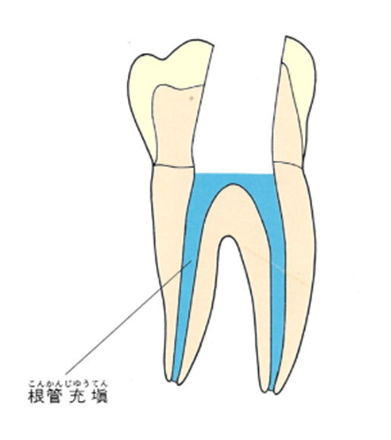

その後神経があった管の中にばい菌が侵入しないように薬を詰めていきます。普通はガッタパーチャポイントと呼ばれる材料とシーラーという薬剤を併用して根管(コンカン)を封鎖します。

水色の部分がガッタパーチャポイントとシーラーです。

虫歯で痛くなると抜髄をします。抜髄して神経をきれいに取った後、ガッタパーチャポイントとシーラーを根管内に入れて根管を封鎖します。ここまでが歯髄炎という病気の治療です。この後は土台を作り、型取りをして冠を被せてその歯の治療は終了です。

ガッタパーチャポイントは、理想的には歯根(シコン)の先ピッタリが良いと言われています。